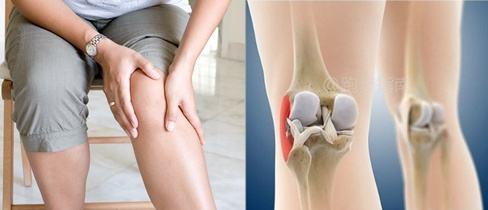

Das Laufknie zeichnet sich durch typische Symptome aus, es handelt sich nicht um eine Degeneration des Knies oder einen Meniskusschaden, es ist so: Gehen ist in Ordnung, Laufen für eine kurze Zeit, dann gibt es Schmerzen und Schwierigkeiten in der Nähe der Außenseite des Knies, man wechselt in den Gehmodus, die Symptome gehen weg, und sobald man läuft, kommen die Schmerzen zurück, was dazu führt, dass man den Laufsport nicht mehr ausüben kann!

LaufknieBezieht sich auf Knieverletzungen, die durch Sportarten wie das Laufen verursacht werden. Typische Symptome sind Schmerzen in der Nähe des Knies, die bei längerem Sitzen mit gebeugtem Knie, beim Treppensteigen oder beim Gehen auf einer kleinen Anhöhe stärker ausgeprägt sind. Sie werden durch sich wiederholende Bewegungen und die Belastung der Gelenkmuskulatur beim Laufen verursacht. Sie tritt nicht nur beim Laufen auf, sondern auch bei anderen Sportarten, bei denen das Knie gebeugt wird, z. B. beim Gehen und Radfahren.

"Laufendes Knie". Bezieht sich auf Knieverletzungen, die durch Sportarten wie das Laufen verursacht werden. Typische Symptome sind Schmerzen in der Nähe des Knies, die bei längerem Sitzen mit gebeugtem Knie, beim Hinabsteigen von Treppen oder beim Gehen auf kleinen Steigungen stärker ausgeprägt sind.